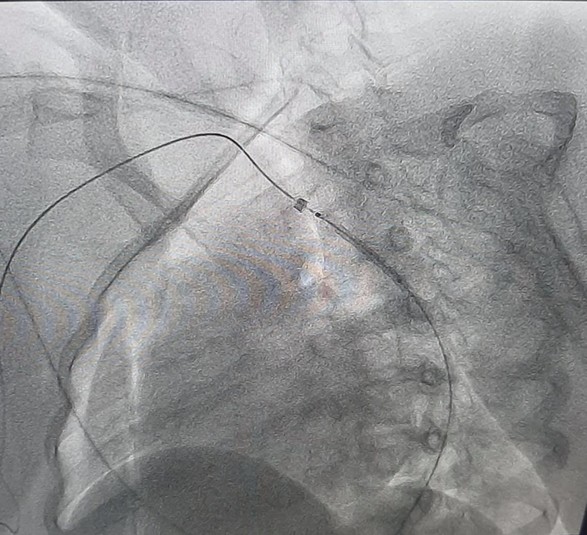

Фото: Клінічна лікарня швидкої медичної допомоги міста Львова

Медики розповідають, що під час обстеження у дівчинки виявили вроджену ваду серця – коарктацію аорти. При такому діагнозі наявне звуження просвіту аорти, внаслідок чого розвивається підвищений тиск у верхній половині тіла.

За допомогою сучасних технологій на основі результатів обстеження була проведена віртуальна реконструкція анатомії аорти та її гілок, що допомогло медикам обрати найбільш сучасну та малотравматичну тактику подальшого лікування.

«Вроджену ваду судини ліквідували за допомогою малоінвазивної ендоваскулярної процедури – встановлення стенту у просвіт судини», – зауважують медики.

Одразу після операції у дитини нормалізувався артеріальний тиск, а також зникла різниця тиску між верхніми та нижніми кінцівками. Повідомляють, що дівчинка почувається абсолютно здоровою, а завдяки обраній тактиці може вже зараз проявляти повну фізичну активність.